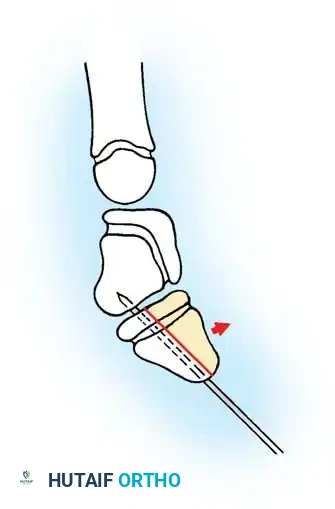

TECHNIQUE 76-52: Release of a Congenital Trigger Finger

Surgical management of a trigger finger requires a more extensile approach due to the high likelihood of complex FDS/FDP interactions.

- Incision: Make a volar zigzag (Bruner) incision centered over the A1 pulley to allow for both proximal and distal exposure of the flexor tendon sheath and its contents.

- Exposure: Elevate the skin flaps, taking care to identify and protect the digital neurovascular bundles bilaterally.

- A1 Pulley Release: Incise the A1 pulley completely from its proximal to distal extent.

- Dynamic Assessment: Passively flex and extend the digit. Inspect the motion of the flexor tendons. If normal gliding of the FDS and FDP is present and triggering has resolved, proceed to closure.

- Extended Exploration (If Triggering Persists):

- Inspect the FDS tendon for a more proximal-than-normal decussation (chiasm of Camper) or an abnormal insertion into the FDP tendon.

- If an abnormal FDS slip is tethering the FDP, excise one or both slips of the FDS tendon to decompress the sheath.

- Inspect the A3 pulley. If triggering occurs at this level, carefully release the A3 pulley, ensuring the A2 and A4 pulleys remain strictly intact.

- Final Verification: Apply proximal traction to both flexor tendons together and individually in the palm, and passively extend the finger to verify complete resolution of triggering.

- Closure: Close the skin with absorbable sutures and apply a soft hand dressing.

Intraoperative view demonstrating the excision of an abnormal FDS slip to relieve persistent triggering after A1 release.

Biomechanical illustration showing the relationship of the FDS and FDP tendons within the digital sheath.